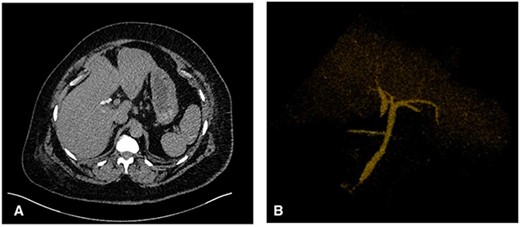

The patient’s postoperative course was uneventful, the drain was removed on postoperative day three. Prior to discharge, a postoperative computed tomography (CT) cholangiogram was performed which revealed the duplicated CHD terminating within the region of the cholecystectomy clips with a communicating aberrant extrahepatic duct (Fig. 3). Subsequently, histopathology had shown chronic cholecystitis with cholelithiasis.

(A) Axial CT image showing the cholecystectomy clips at the base of a duplicated CHD with the corresponding CHD on the medial aspect. (B) 3D reconstruction demonstrating the CHD duplication with a single distal draining CBD.